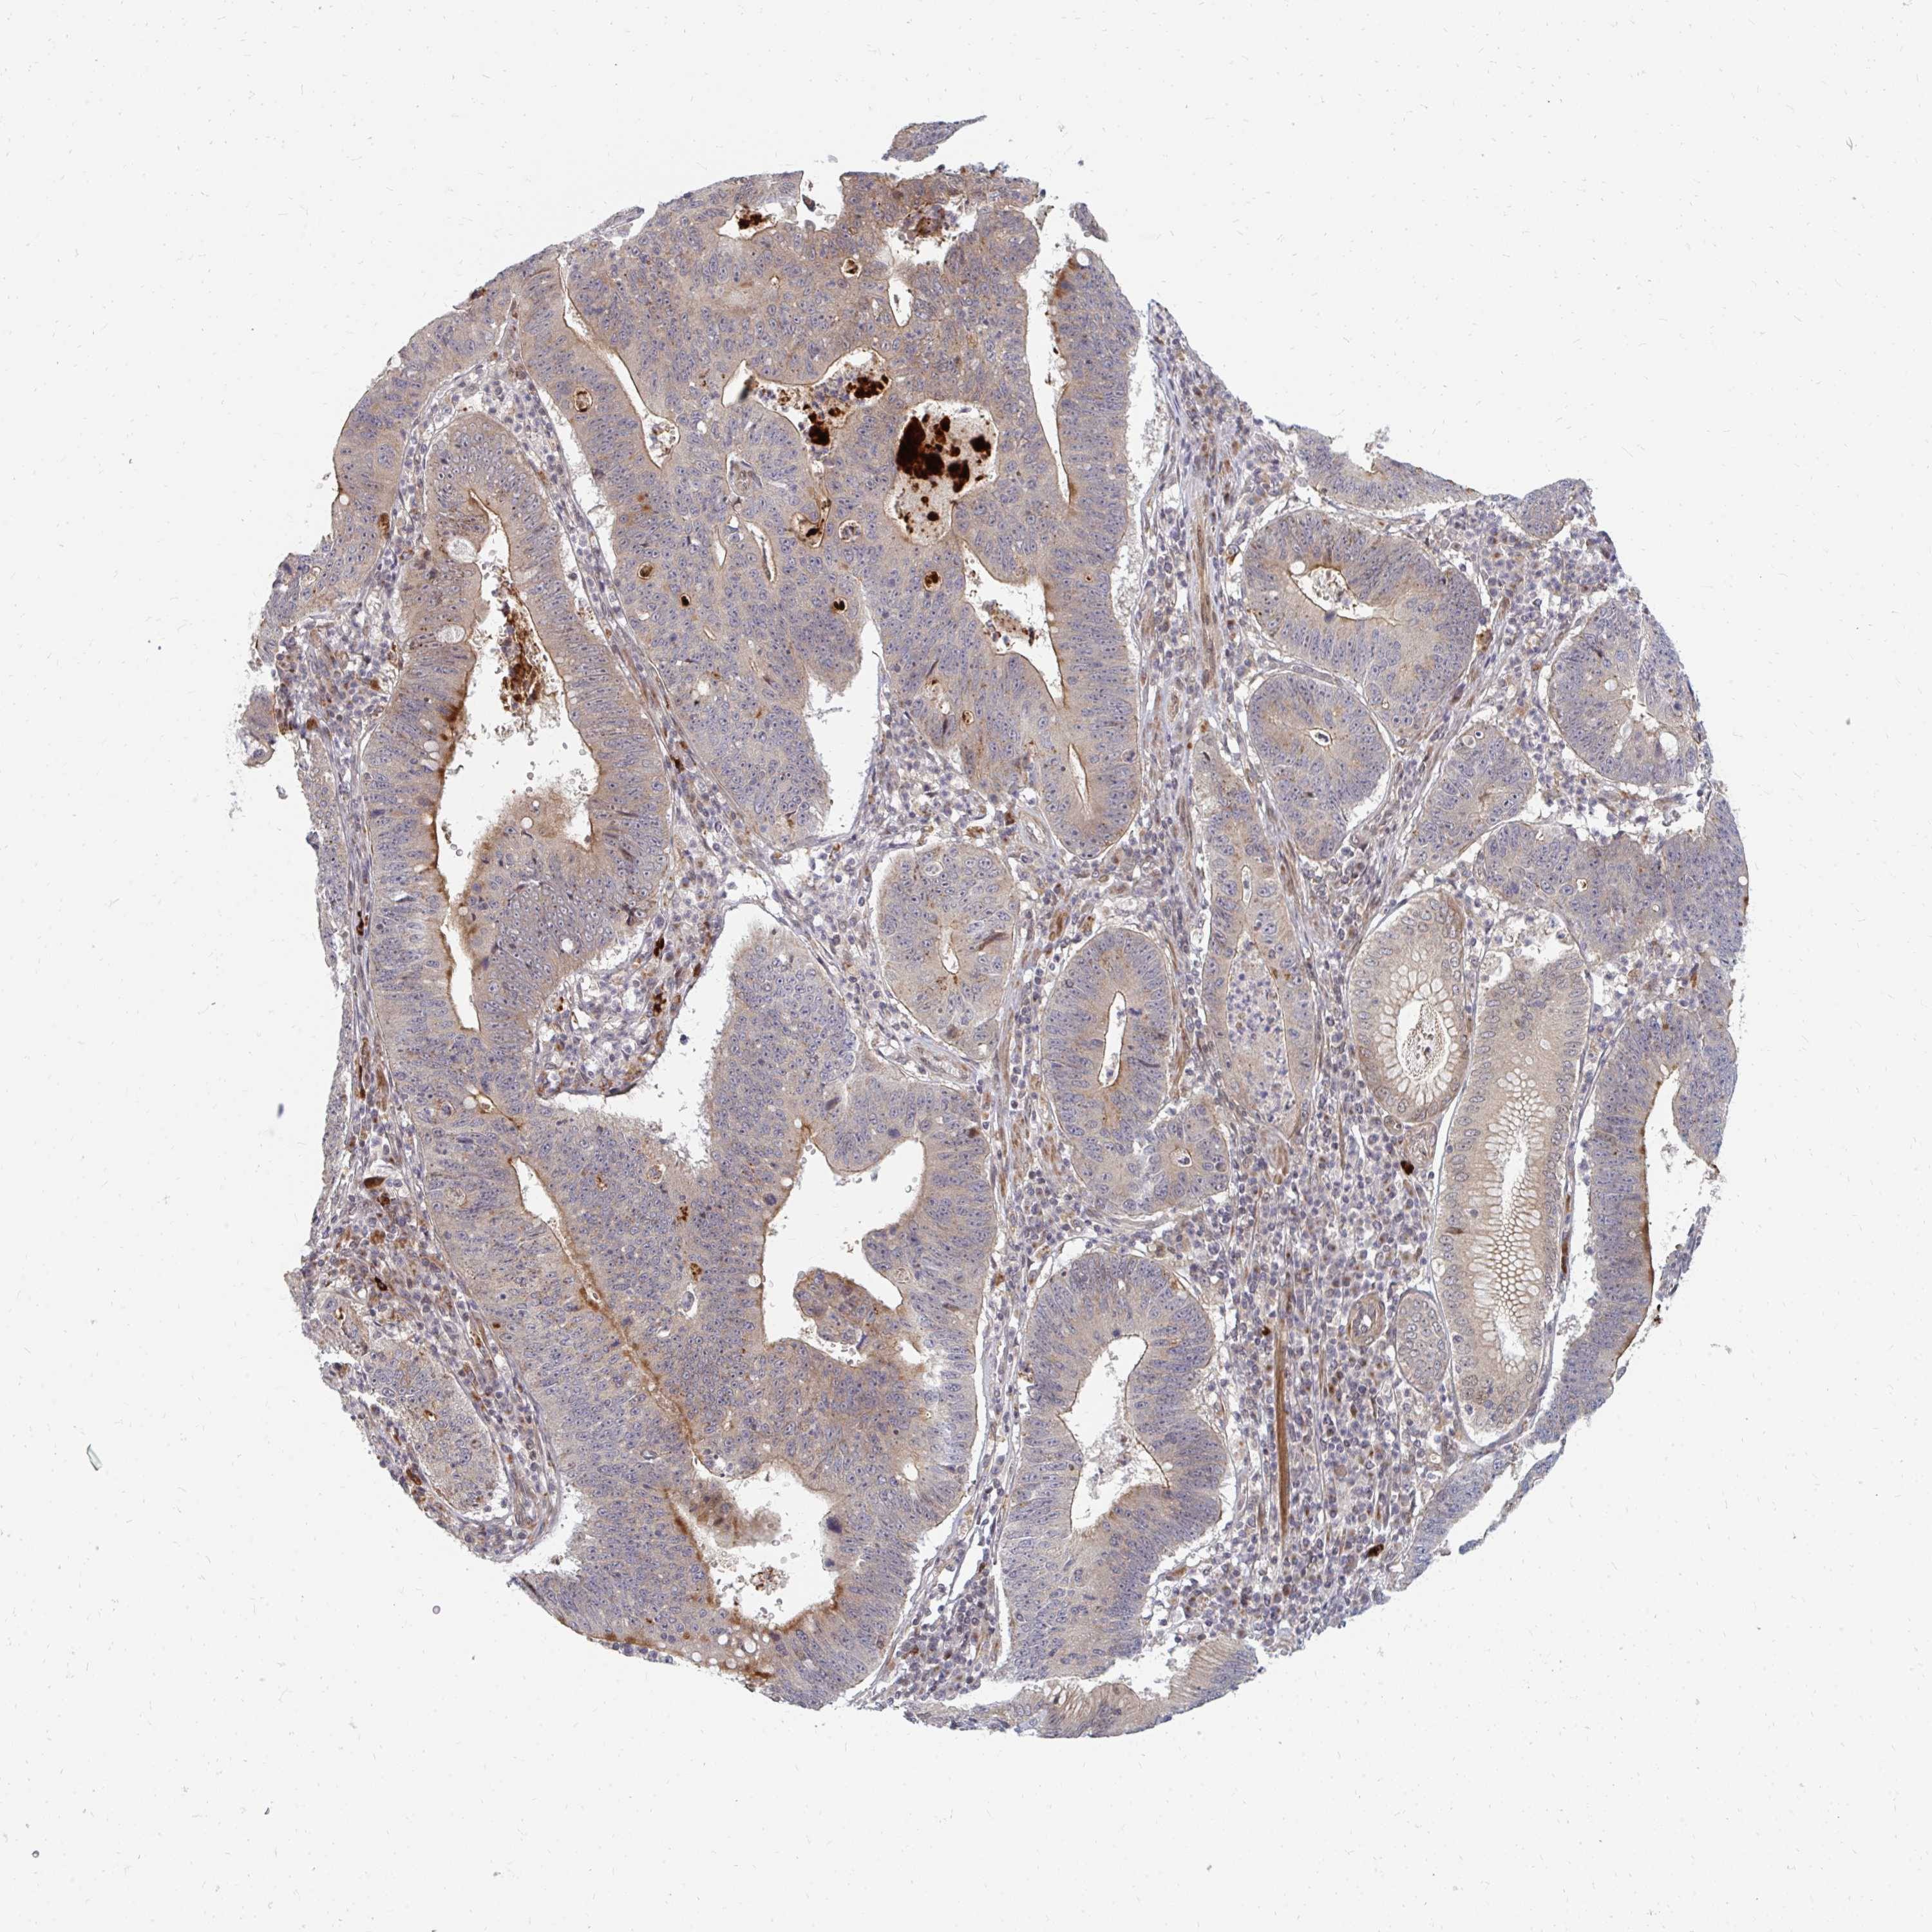

STOMACH CANCER - Protein expressioni

A mouse-over function shows sample information and annotation data. Click on an image to view it in a full screen mode. Samples can be filtered based on level of antibody staining by selecting one or several of the following categories: high, medium, low and not detected. The assay and annotation is described here.

Note that samples used for immunohistochemistry by the Human Protein Atlas do not correspond to samples in the TCGA dataset.

Antibody stainingi

Antibody staining in the annotated cell types in the current human tissue is reported as not detected, low, medium, or high, based on conventional immunohistochemistry profiling in selected tissues. This score is based on the combination of the staining intensity and fraction of stained cells.

Each image is clickable and will lead to virtual microscopy that enables deeper exploration of all samples and also displays staining intensity scores, fraction scores and subcellular localization as well as patient and tissue information for each sample.

Antibody HPA046100

Antibody HPA049212

Staining

High

Medium

Low

Not detected

Intensity

Strong

Moderate

Weak

Negative

Quantity

>75%

75%-25%

<25%

None

Location

Nuclear

Cytoplasmic/membranous

Cytoplasmic/membranous,nuclear

Adenocarcinoma, NOS